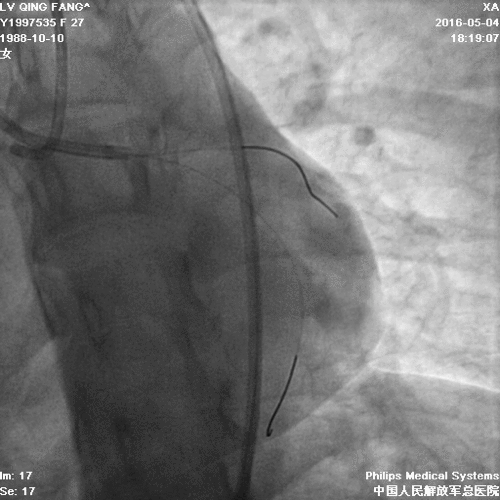

• PCI难点:需要同时开通前降支和回旋支;

• 手术难度大、前降支和回旋支闭塞,前降支闭塞段长,开通一支可能性大,同时开通难度大。

PCI